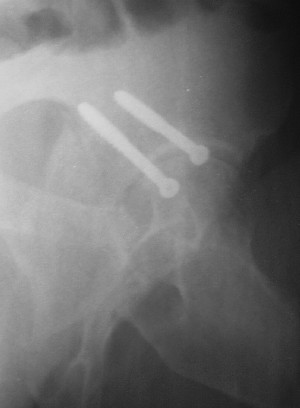

Считаю, что в представленном Вами случае целесообразно подумать о первичном протезировании. Привожу пример более легкого повреждения, где потерял время надеясь спасти сустав.

19/05/03

Больной 18 мая 2003 года в автоаварии получил перелом левой вертлужной впадины, вывих бедра. Госпитализирован в один из стационаров области.Вывих вправлен. В последствии бедро вывихивалось еще дважды. На консультацию был представлен снимок от 19.05.03г., больной переведен к нам 3.06.03г. Снимок при поступлении - перелом впадины, задне-верхний вывих бедра. 05.06.2003 г. выполнено открытое вправление вывиха левого бедра и остеосинтез стенки вертлужной впадины двумя винтами. Послеоперационный период без осложнений. Объем движений в левом тазобедренном суставе восстановился полностью. Выписан на амбулаторное лечение в удовлетворительном состоянии с рекомендациями 3 месяца ходить на костылях без нагрузки на оперированную конечность. На контрольных рентгенограммах левого тазобедренного сустава 13.10.2003 г. - признаки консолидации перелома; плотность, форма головки и состояние суставных поверхностей удовлетворительные. Разрешена дозированная осевая нагрузка, на конечность с использованием дополнительной опоры. 19.12.2003 г. больной обратился с жалобами на боли в левом тазобедренном суставе. На рентгенограммах левого тазобедренного сустава 19.12.2003 г., 20.02.04г. - асептичекий некроз головки бедра. 5.04.04г. - эндопротез. Сейчас ходит без трости, не хромает. Особенность эндопротезирования - при удалении винтов прослежена линия перелома заднего края впадины и предложено установить чашку несколько меньшего диаметра, чтобы она была покрыта несломанной частью.